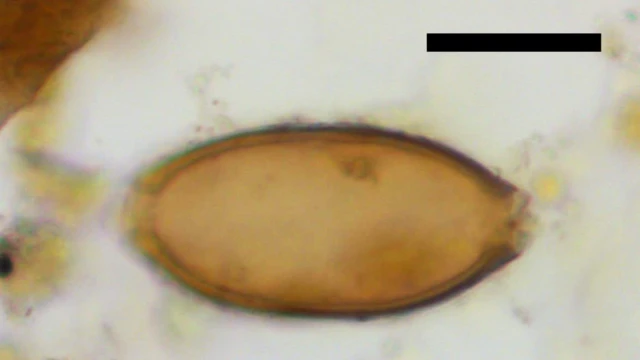

Los investigadores hallaron huevos de parásitos intestinales llamados tricocéfalos o gusanos látigo (Trichuris trichiura).

Se trata de la evidencia arqueológica más antigua de infección por parásitos intestinales en el Cercano Oriente.

Los gusanos látigo pueden alcanzar entre 30 y 50 milímetros de longitud.

Viven adheridos al intestino grueso donde pueden llegar a poner más de 5.000 huevos al día.

La infección puede causar anemia, enfermedades intestinales y dolor, además de defecaciones con sangre.

"Fue un momento especial identificar los huevos del parásito con más de 8.000 años de antigüedad", señalo Evelena Anastasiou, coautora del estudio publicado en la revista Antiquity.